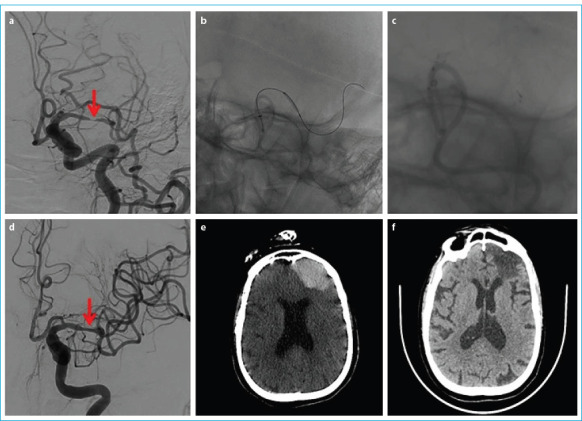

目的:评价有症状的颅内狭窄患者对药物干预反应不充分的血管内治疗的疗效和临床结果。方法:该研究纳入了32例于2021年12月至2023年12月期间因颅内高级别(70%-99%严重程度)动脉粥样硬化性狭窄接受血管内治疗的患者。患者在最近三周内未发生任何急性缺血性或出血性梗死,基线时改良兰金量表评分≤3分,尽管接受了最好的药物治疗,但仍发生过短暂性缺血性发作或非致残性卒中。记录技术和临床成功率、死亡率和并发症发生率。结果:纳入研究的32例患者中,男性占62.5% (n=20),平均年龄66.4±10.09岁。43.8% (n=14)的患者行颅内颈内动脉支架植入术,37.5% (n=12)的患者行硬膜内椎动脉支架植入术,12.5% (n=4)的患者行大脑中动脉支架植入术,6.3% (n=2)的患者行基底动脉支架植入术。技术成功率100%,临床成功率87.5%。术前平均狭窄度为91.7±6.3%,术后残余狭窄度为22.1±4.7%。Neuroform Atlas®支架系统18例(56.3%),Credo®支架8例(25%),冠状动脉球囊可扩张支架4例(12.5%),LVIS®支架系统2例(6.3%)。28例(87.5%)患者在前30天没有任何症状,2例(6.2%)患者发生缺血性卒中,1例(3.1%)患者发生出血性卒中,1例(3.1%)患者死亡。结论:在精心挑选的患者中进行血管内治疗,量身定制的治疗亚型选择,以及一个经验丰富的多学科团队在手术前、手术中和手术后对患者进行监督,有可能为有症状的颅内动脉粥样硬化性狭窄患者提供安全有效的治疗。

Results: Of the 32 patients included in the study, 62.5% (n=20) were male, and the mean age was 66.4±10.09 years. Stenting was performed on the intracranial internal carotid artery in 43.8% (n=14) of the patients, the intradural vertebral artery in 37.5% (n=12), the middle cerebral artery in 12.5% (n=4), and the basilar artery in 6.3% (n=2). The technical success rate was 100%, and the clinical success rate was 87.5%. The mean degree of stenosis before the procedure was 91.7±6.3%, and the degree of residual stenosis after the procedure was 22.1±4.7%. The Neuroform Atlas® stent system was used in 18 cases (56.3%), Credo® stents in eight (25%), coronary balloon-expandable stents in four (12.5%), and the LVIS® stent system in two (6.3%). Twenty-eight (87.5%) patients did not have any symptoms in the first 30 days, while two (6.2%) patients had an ischemic stroke, one (3.1%) patient had a hemorrhagic stroke, and one (3.1%) died.